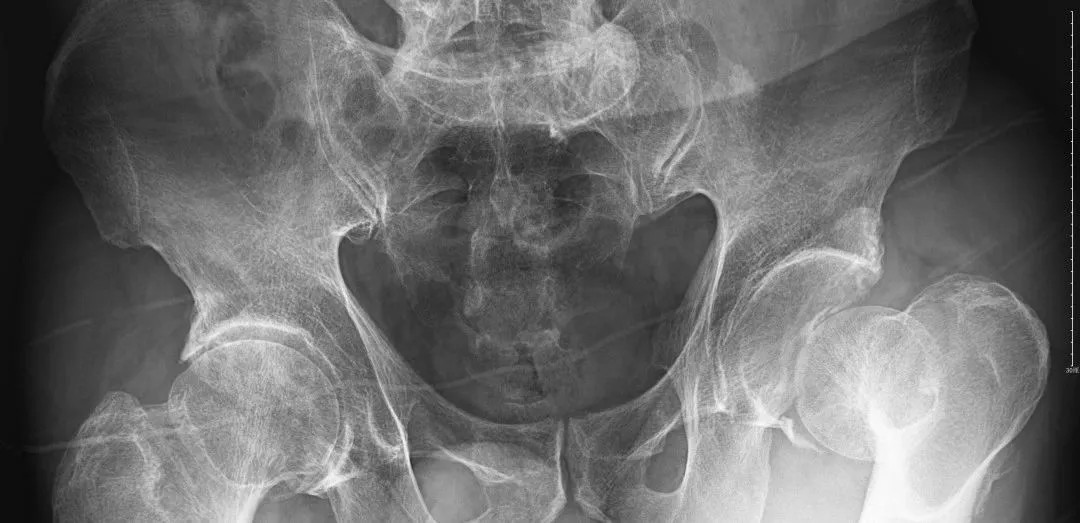

(術(shù)后復(fù)片  關(guān)節(jié)對位良好)